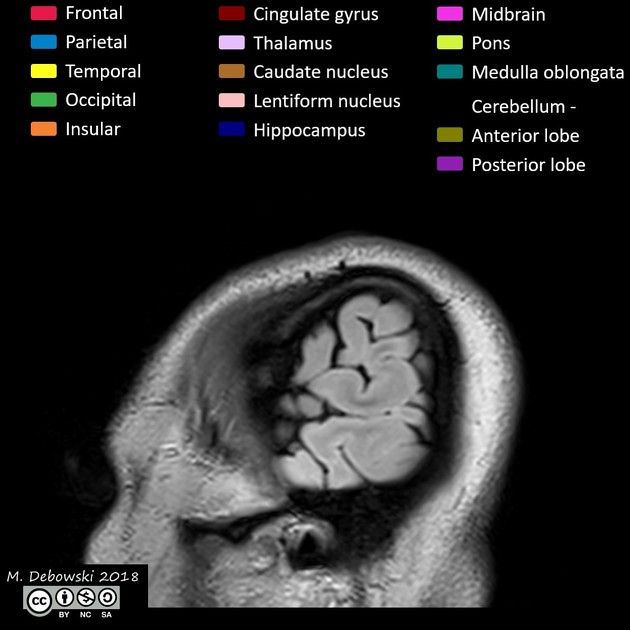

GIẢI PHẪU CẮT LỚP MRI SỌ NÃO - SAGITTAL